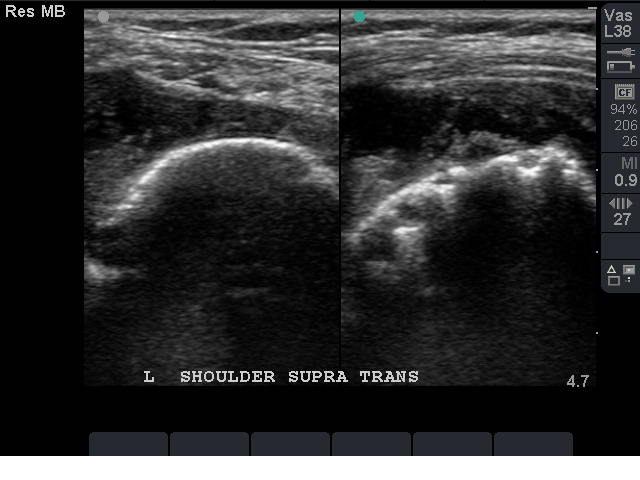

Supraspinatus Tendon transverse axis: note the dark hypoechoic rim above the cortical surface (articular cartilage), this indicates the probe position is over the proximal Supraspinatus

Distal Supraspinatus at its insertion, note the hypoechoic rim above the cortex is absent, image is now over the Greater Tuberocity. The defect in the tendon on this image is at the anterior margin of the tendon at the border of the biceps tendon.

Supraspinatus Long axis: note the defect at the Greater Tuberocity surface. This image is taken at the mid long axis. It is important to sweep the probe anteriorly until the long axis bicep is seen.

Bringing the probe anteriorly may show more pathology, also rocking the probe heavier on the distal